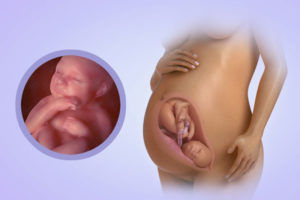

По сравнению с 18 неделей, малыш подрос – его рост достиг 15 сантиметров. Пропорции его тела почти такие, какими будут при рождении. Бедро малыша имеет длину 3 см, голень от 2-х до 3-х см. Тело ребенка активно накапливает жир.

Плод активно развивается и совершенствуется. Его размер достигает 25 см, а масса составляет примерно 350 граммов. Внутренние органы и системы продолжают развиваться. Организм готовится к автономному существованию – особенно стремительно развиваются нервная система и головной мозг.

На сроке 19 недель, малыш способен поднимать головку и поворачивать ее в разные стороны. Средний вес плода составляет 250 г.